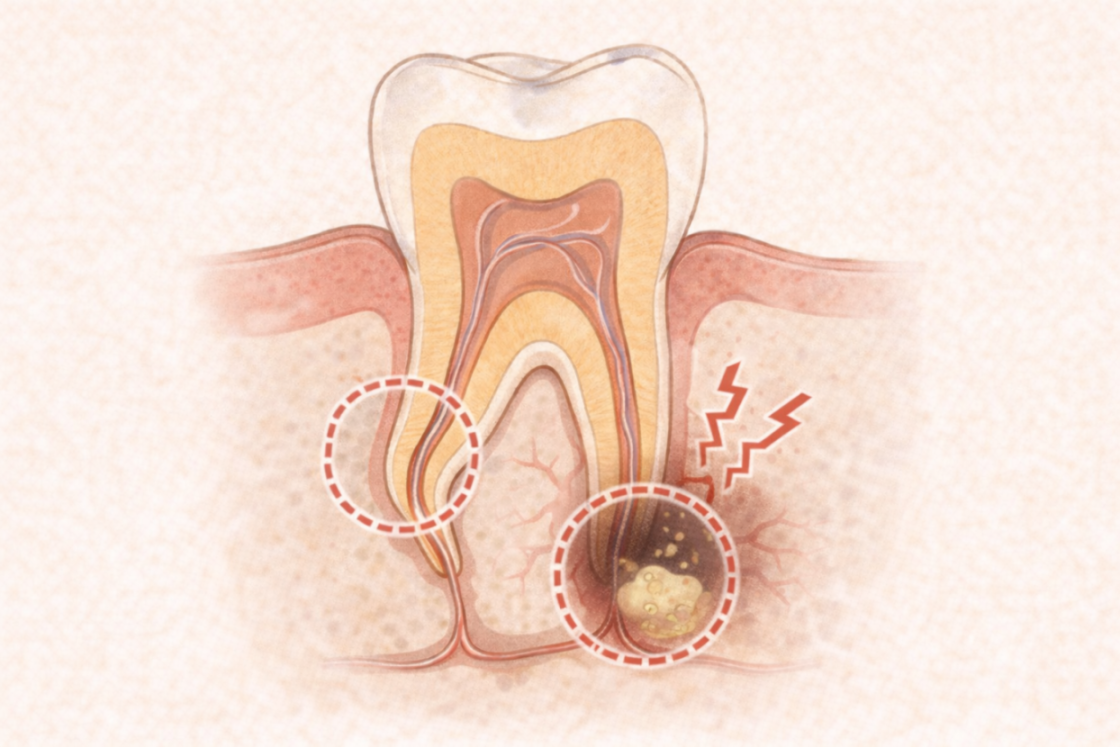

③ 細菌感染がひどい・治療中に痛みがある

根の中に細菌が多いと、薬剤を入れるときに痛みが出たり、

痛みが強い状態では次の工程に進めないことがあります。

炎症が強いほど時間が必要になるのはこのためです。

■ 根管治療は“精度”が命。だから手を抜けません

根の治療は、見えない狭い空間の細菌をゼロに近い状態まで減らす治療。

少しでも菌が残れば再発し、

「また痛い」「腫れた」「結局抜歯に…」となってしまいます。

そのため、

根管治療はいい加減に進めることができません。

1回1回の処置に時間と正確さが求められます。